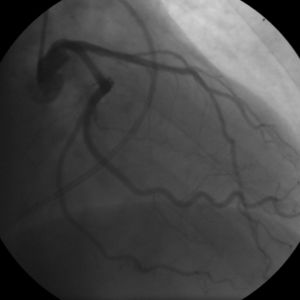

يمكن اعتبار مرض تصلب شرايين القلب مجموعة من الأمراض التي تصيب القلب. واحدة من هذه صور هذا المرض هو شخص بلا أعراض وجدران شرايين قلبه التاجية مبطنة من الداخل بخطوط من الدهون atheromatous streaks. يمثل ظهور هذه الخطوط المرحلة الأولى من مرض القلب التاجي ولكنها لا تعيق تدفق الدم خلال الشريان. إذا تم عمل تصوير الشرايين التاجية Coronary Angiogram خلال هذه المرحلة من المرض فانه من المحتمل ألا يظهر أي دليل على وجود مرض تصلب الشرايين القلبية وذلك لان قطر تجويف الشريان لم يقل. خلال عدة سنوات، تزداد هذه الخطوط الدهنية سماكة، وازدياد سماكتها مبطِنة جدار الشريان يؤدي في النهاية إلى صغر تجويفه وبالتالي يعوق مسار الدم خلاله. اُعتقد في السابق أن عملية تكوّن الصفائح الدهنية عملية بطيئة وتدريجية، لكن ظهرت دلائل حديثة على أن التكون التدريجي لهذه الصفائح يُسرّعُه تمزقات صغيرة تحدث فيها مما يؤدي إلى ازدياد حجم الصفيحة الدهنية نتيجة تراكم المواد المتخثرة عليها. من النادر أن تسبب الصفائح الدهنية التي تسد أقل من 70 في المائة من تجويف الشريان أعراض مرض انسداد الشرايين التاجية. في حال ازدياد حجم الصفيحة مسببة انسداد الشريان بنسبة تزيد عن 70 في المائة، تظهر في الشخص في هذه المرحلة أعراض انسداد الشرايين التاجية. يمكن القول في هذه المرحلة من المرض أن الشخص لديه مرض نقص التروية القلبية ischemic heart disease. تُلاحظ أولى أعراض مرض نقص التروية القلبية خلال الأوقات التي يزيد فيها الضغط على عمل القلب. كمثال على ذلك، الم الذبحة الصدرية الجُهدية exertional angina أو تراجع قدرته على تحمل التمارين البدنية. قد يتطور المرض فيما بعد ليصل إلى الحد الذي يُسد فيه تجويف الوعاء الدموي بشكل شبه كامل، معيقاً وصول الدم حامل الأكسجين إلى عضلة القلب. المصابون بهذه الدرجة من مرض الشريان التاجي يكونون قد عانوا من جلطة قلبية (ذبحة صدرية) مرة أو اثنتان، وقد يكون لديهم أعراض أو علامات مرض الشريان التاجي المزمن، متضمنا الم الذبحة الصدرية بدون أي مجهود بدني angina at rest أو الاستسقاء الرئويflash pulmonary edema. يجب أن يتم التمييز بين كلٍ من مرض نقص التروية القلبية myocardial ischemia والجلطة القلبية (احتشاء عضلة القلب) myocardial infarction. نقص التروية معناه أن كمية الأكسجين التي تصل إلى عضلة القلب غير كافية لتلبية احتياجه. عندما تنقص تروية عضلة القلب فإنها لا تعمل بالشكل الأمثل، وإذا نقصت التروية لمساحة كبيرة من عضلة القلب فان ذلك قد يؤدي إلى عدم قدرة العضلة على الانقباض والانبساط. إذا تحسن تدفق الدم إلى العضلة فان نقص التروية يمكن عكسه. بينما الجلطة القلبية معناها أن نسيج العضلة قد مات ولا يمكن عكس ذلك لقلة تدفق الدم المشبع بالأكسجين إليها. قد يحدث للشخص تمزق للصفيحة الدهنية في أي مرحلة من مراحل المرض. التمزق المفاجئ للصفيحة قد يؤدي إلى جلطة قلبية مفاجِئة (ذبحة صدرية).

- Coronary angiography